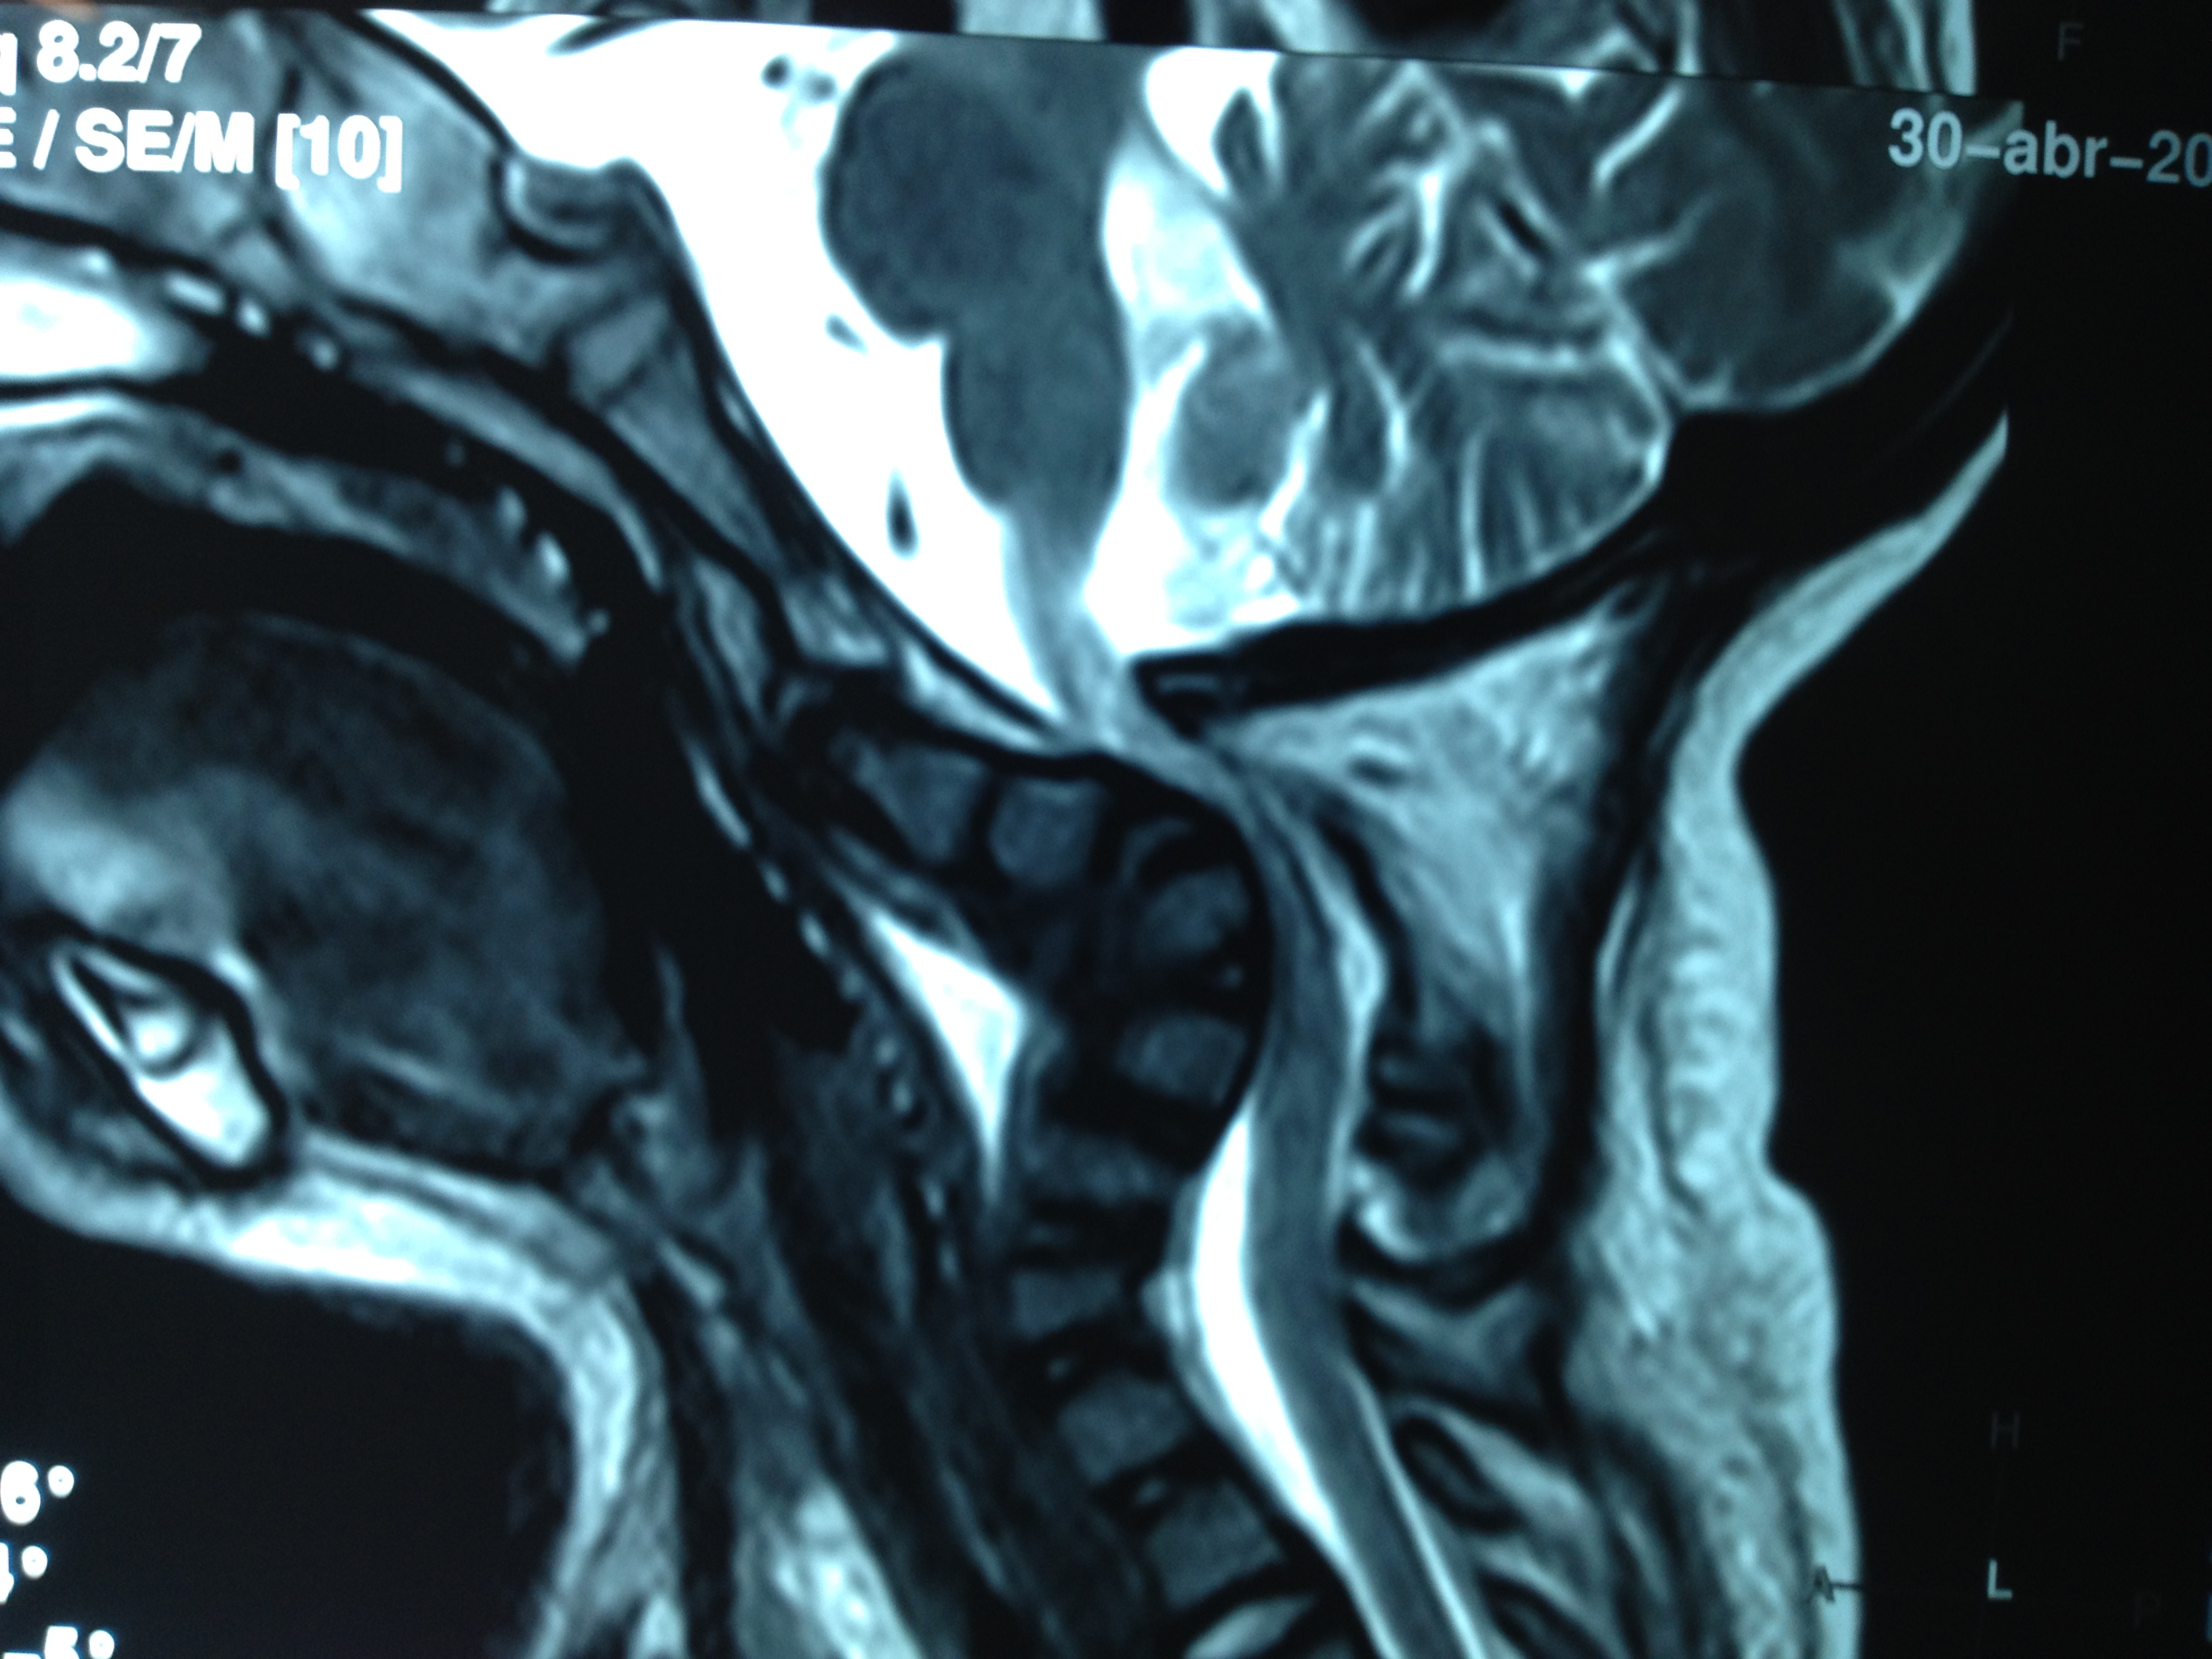

- Figura 13. Cifosis cervical asociada a compresión medular

- Figura 8 A. Resonancia Magnetica. Compresión medular severa y mielomalacia asociada.